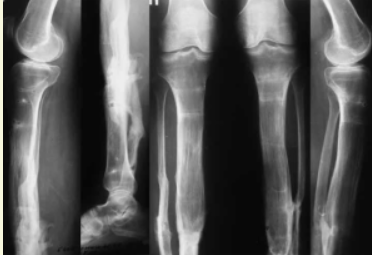

Влияние полиморфизма генов IL-17A и PPARG на течение гнойных осложнений после лечения пострадавших с травмами костей нижних конечностей

острые травматические повреждения коленного сустава, голени, голеностопного сустава и стопы (переломы, вывихи, разрывы связок) в анамнезе;

наличие гнойно-воспалительных осложнений (остеомиелит, гнойный артрит, флегмона, абсцесс), развившихся в процессе лечения и в течение первого года после лечения;